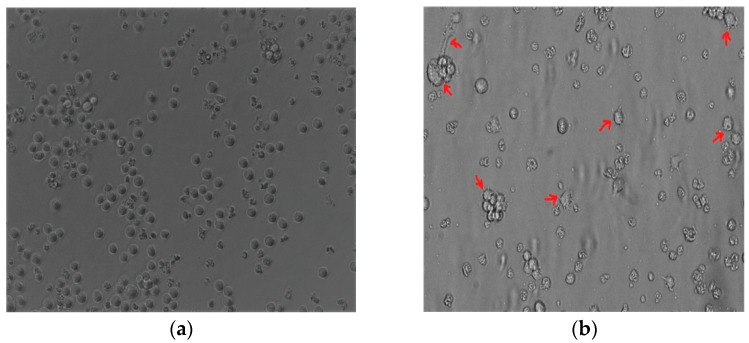

Methods: We treated THP-1-like macrophages with 100 nM Ang II for 24 h. The culture media thus obtained was used as conditioned media and applied at 50% on MCF-7 and MDA-MB-231 breast cancer cell lines. The effects of the conditioned media on cancer cell lines were then investigated by various methods such as a cell proliferation assay, migration assay, polarization assay, and by the detection of apoptosis and reactive oxygen species (ROS) generation.

Results: We demonstrated that in vitro Ang II promotes macrophage polarization toward proinflammatory M1-like macrophages and anti-inflammatory M2-like macrophages. Interestingly, Ang II, through macrophages, showed varied effects on different breast cancer cell lines, promoting tumor growth and progression in MCF-7 while inhibiting tumor growth and progression in MDA-MB-23.